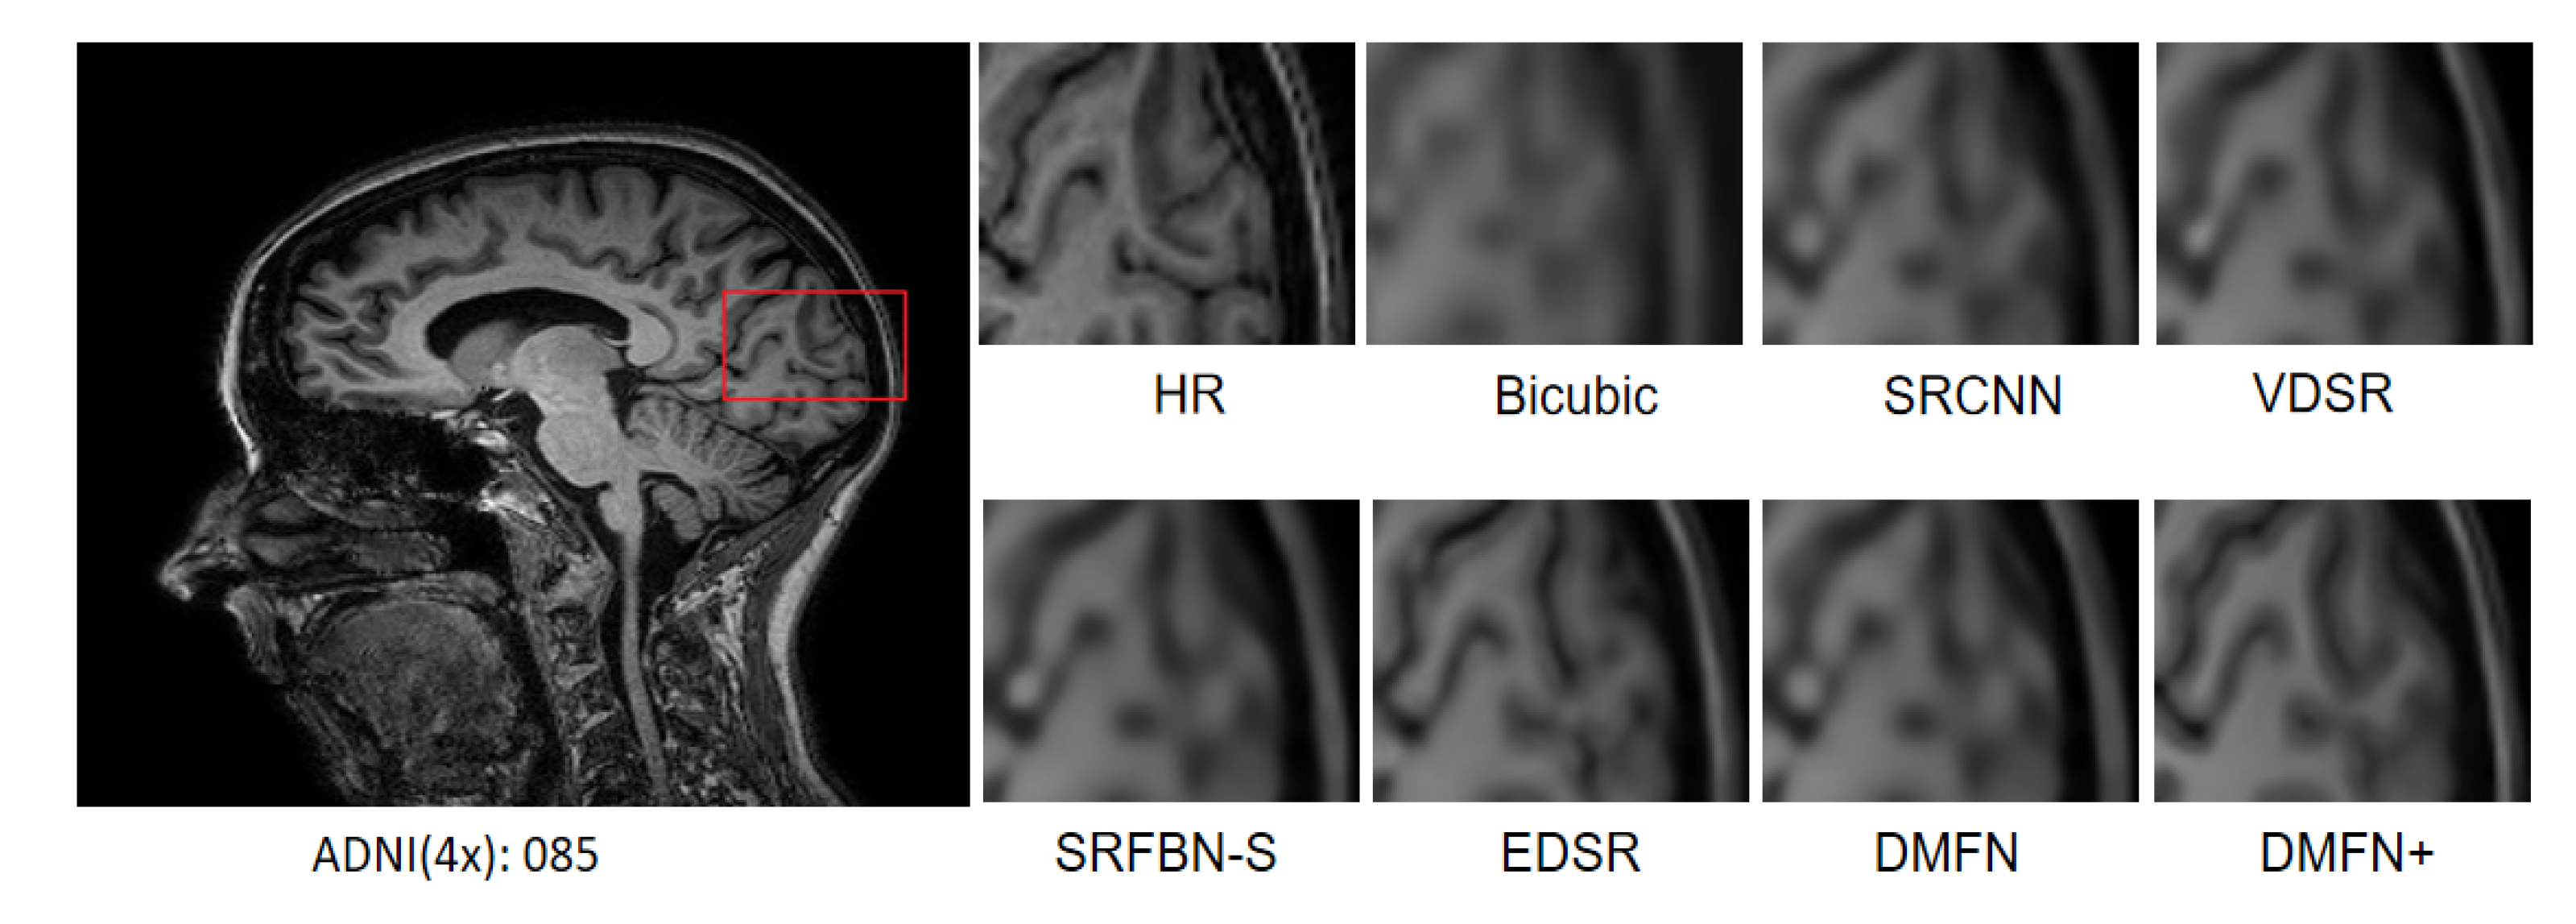

4.7. Comparison with Classical SR Methods